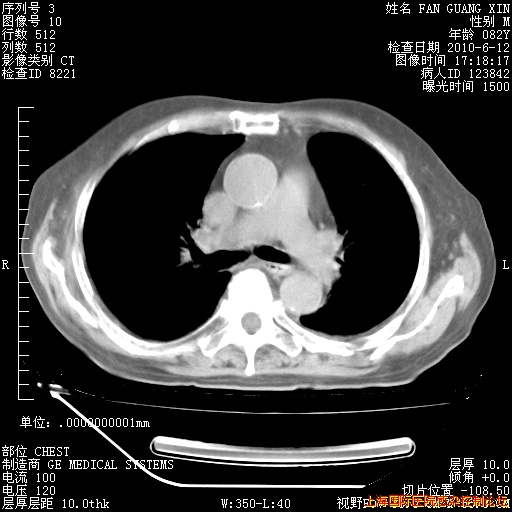

6月12日肺窗

整整相隔30天的肺部CT好像有所好转啊。甲强龙减量第3天,需要观察体温。